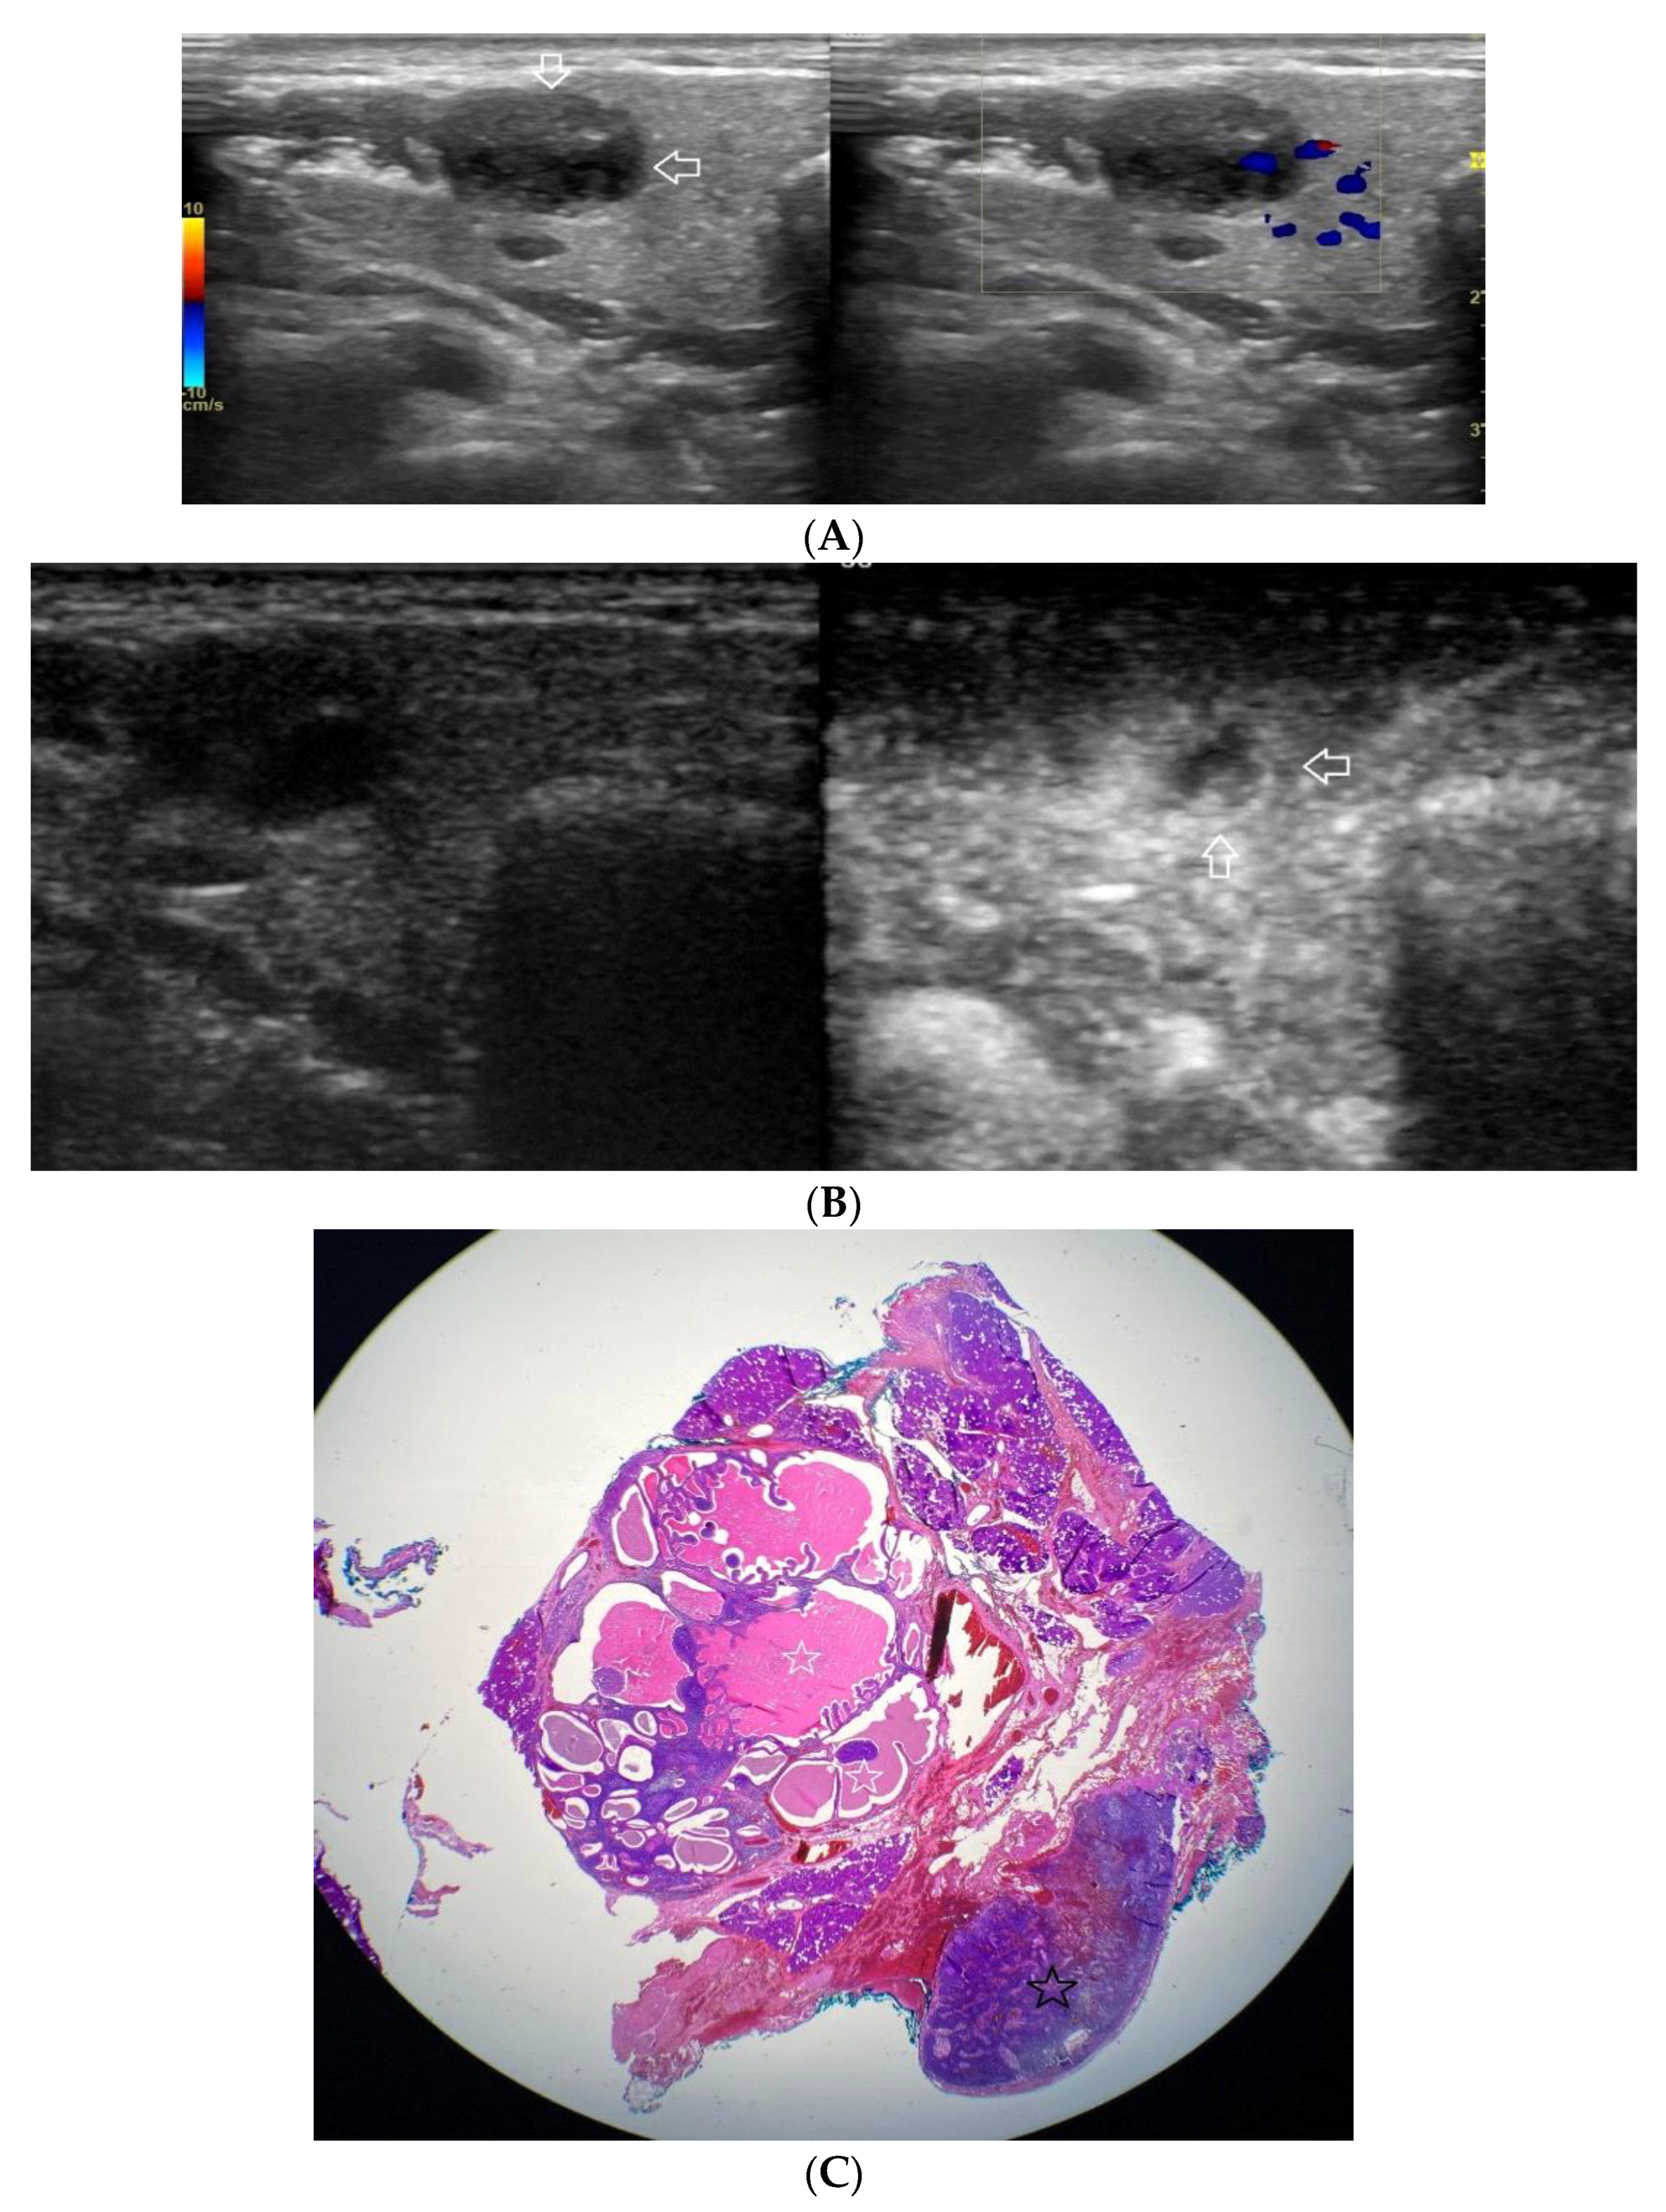

Figure 4.

(A−C) Warthin’s tumour. (A) Routine ultrasonographic examination in B presentation and colour Doppler: a big hypoechogenic well-demarcated focal lesion of a heterogeneous echostructure (white arrows). On CD, a low blood flow is observed. (B) Contrast-enhanced imaging in arterial phase: a strong homogeneous enhancement of a peripheral part of the lesion (white arrows). In the central part of the tumour, irregular areas without enhancement. (C) Pathomorphological image, H & E stain. Large areas of irregular shape containing fluid (white stars). A part containing glandular tissue located peripherally.